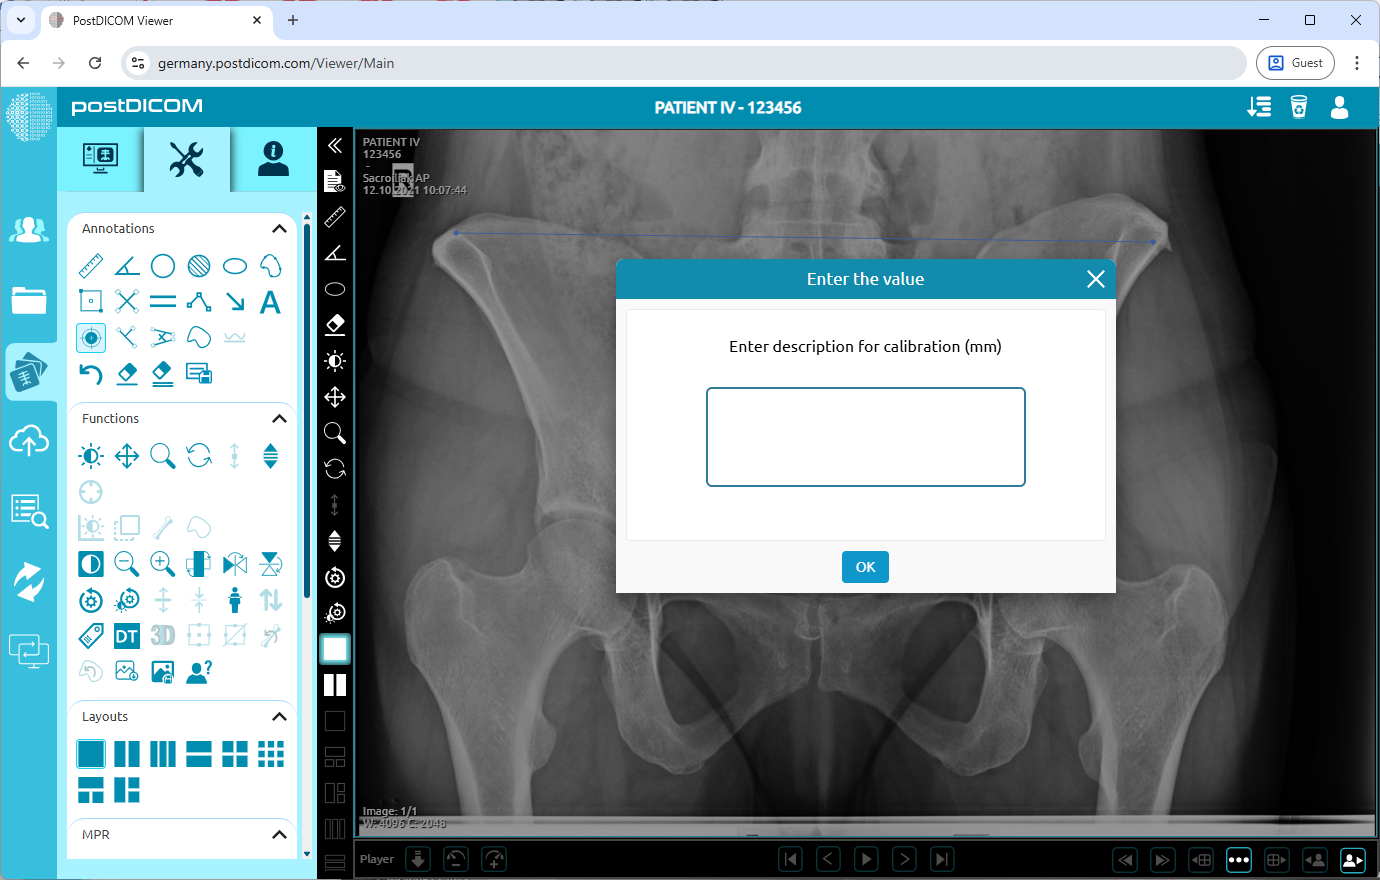

After drawing the line, a dialog box will appear. Enter the actual known size (in mm). Once calibration is set, Then all measurements you will do calculates with this calibration.